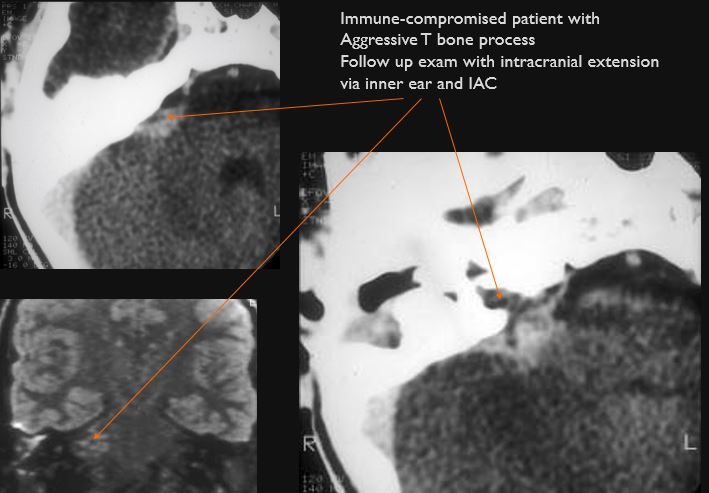

The inner ear, in particular the lateral semicircular canal and the cochlea are eroded or otherwise abnormal. [Yes/No]

There is dural reactive or leptomeningeal enhancement involving the internal auditory canal and the 7th and 8th cranial nerves. [Yes/No]

There is brain edema and/or evolving abscess present or, specifically, involving the inferior temporal lobe or adjacent cerebellum. [Yes/No]